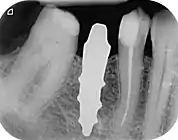

RAIs are custom made to perfectly fit the tooth socket of a specific patient immediately after tooth extraction. Therefore every implant is unique. As an optimized root-form it is much more than a simple 1:1 replica of a tooth. Since it exactly fills the gap left after the tooth is extracted, surgery is rarely needed. The implant can be produced from a copy of the extracted tooth, an impression of the tooth socket, or from a CT scan or CBCT scan.[3] The advantage of a CBCT scan is that the implant can be produced before extraction. With the former methods, it takes one or two days to fabricate an implant.

A root analogue implant can be fabricated from zirconium dioxide (zirconia) or titanium. Successful titanium RAIs have been three-dimensionally printed as porous one-piece implants, using CAD software.[4] However, zirconia is the preferred material, because it is more esthetic in color, with no grey discoloration visible through gums.[5][1]

- Natural form: a custom milled anatomic implant replicates the natural form of a tooth, so it simply fits into the tooth socket. Like the original tooth, a root analogue implant can have single- and multi-rooted forms.

A new attempt was made by Pirker et al 2004 in a human trial with root analogue zirconia implants, but this time by applying differentiated osseoingration on the surface. In 2011 he reported 90% success rate with this method in a 2.5 year human trial.[11]